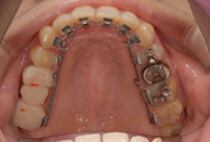

インビザライン、急速拡大装置(MSEⅡ) 、インプラントアンカー、スタンダードブラケット

上顎は急速拡大、下顎はコルチコトミーと人工骨で歯茎が下がるのを予防しつつスピーディーな移動ができるようにしました。